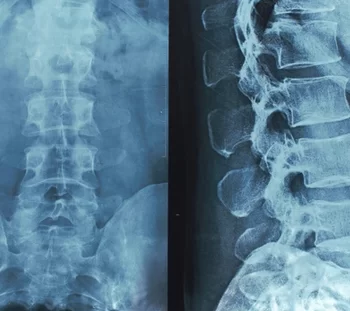

Χειρουργική Σπονδυλικής Στήλης

Η συγχρονη χειρουργική του εγκεφάλου συνδυάζει τις ελάχιστα επεμβατικές τεχνικές με τις σύγχρονες τεχνικές χαρτογράφησης των λειτουργιών του εγκεφάλου. Ο στόχος είναι η αποκατάσταση της υγείας του ασθενούς και η διατήρηση όλων των πολύτιμων λειτουργιών.